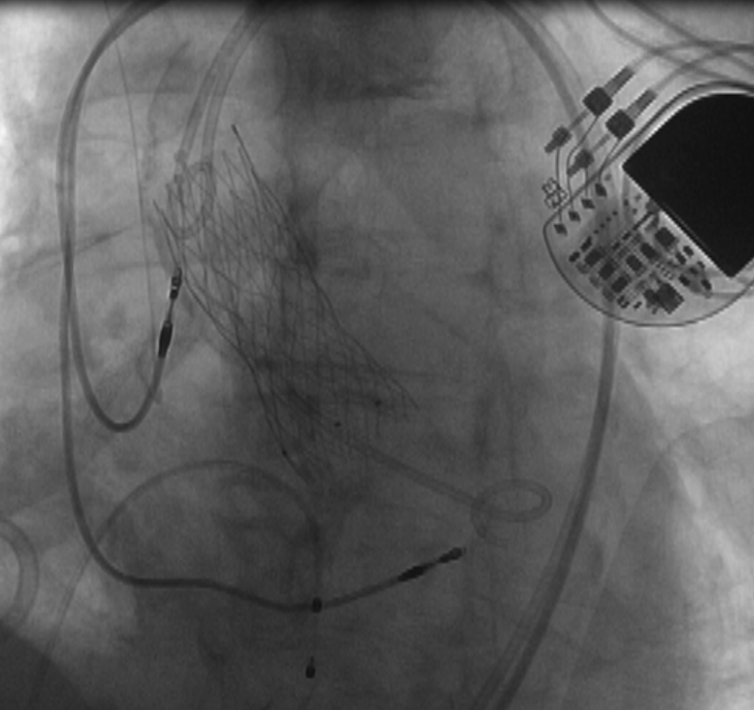

术后影像图

在与患者家属充分沟通并取得理解和同意后,郭延松教授带领团队联合重症医学科、麻醉科、超声科、放射科、心血管外科、手术室等多学科对手术策略及围手术期可能出现风险所制定的预案进行反复研究讨论后,决定为患者选择经皮导管主动脉瓣置入术+经皮冠脉内支架植入术,解除主动脉瓣重度狭窄,打通心脏血管的阻塞,恢复患者正常的血液循环和血流动力学,经过团队的精心操作,成功为患者修复主动脉。

经皮导管主动瓣置入术

该术式是目前治疗主动脉疾病的先进诊疗技术,无需开胸,仅需通过股动脉6mm穿刺点即可完成主动脉瓣置换,恢复瓣膜原有的正常开闭功能,极大改善患者的生活质量。我院自开展经皮导管主动脉瓣置入术以来,通过多学科团队合作已成功为众多主动脉瓣重度狭窄患者实施经皮导管主动脉瓣置入术治疗,其中80岁以上患者占比近三分之一,90岁及以上患者共5位,目前手术例数及操作水平居全国前列,为心脏瓣膜病患者带来福音。